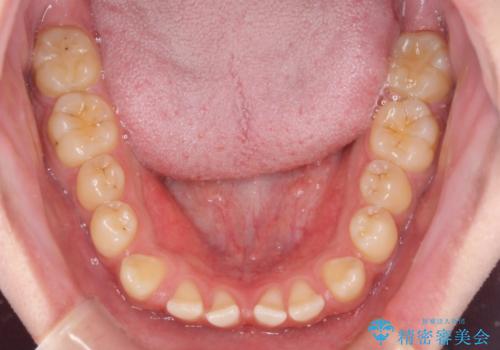

空隙歯列を閉じる 舌のトレーニングとワイヤー矯正

- 上下前歯の隙間を気にして来院された患者様です。

飲み込みや話をするときに舌を突出させる癖が強くあり、それが原因でスペースが空いていました。

舌癖を改善するためのトレーニングを行いながら、ワイヤー装置を用いて前歯の隙間を閉じていくこととしました。

舌の突出癖がなかなか改善されず、治療期間は当初予定よりも大分長くなりました。

装置除去を予定していた日に、油断されたのか1mmほどのスペースを作ってしまったため、除去が3ヶ月延長されたことで、舌のトレーニングの重要性を理解していただきました。

装置除去後もトレーニングを継続されているようで、後戻りによるスペースは今のところ認められておりません。